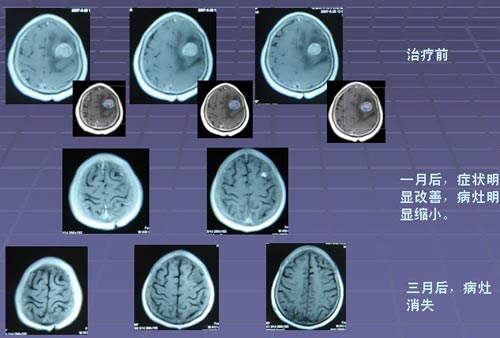

• 肺癌脑转移五年生存率

肺癌脑转移五年生存率

在大多数人的意识里,癌症就代表着绝望与死亡。但据中国工程院院士、中国医学科学院肿瘤医院孙燕教授2011年介绍:肿瘤科医生患癌后, 80%都得到了治愈(5年生存)特别是一些发生 肺癌脑转移 ,目前依然带瘤生存。。而国家癌症中心全国肿瘤防治研究办公室 ...